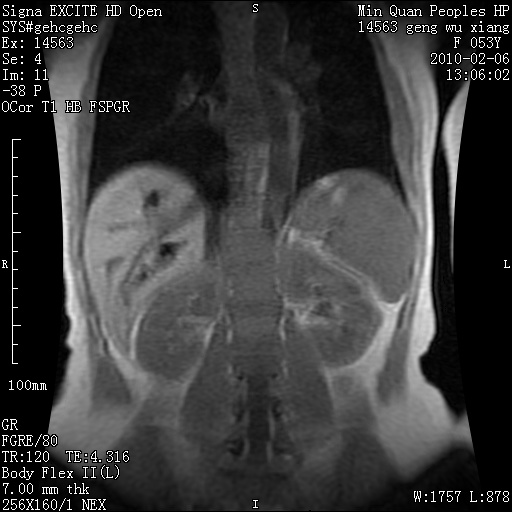

标题: MRI2762:胆道梗阻原因?

f,53y,全身黄染多日。

高位胆道梗阻 胆管癌可能性大

支持 高位胆道梗阻 胆管癌可能性大。